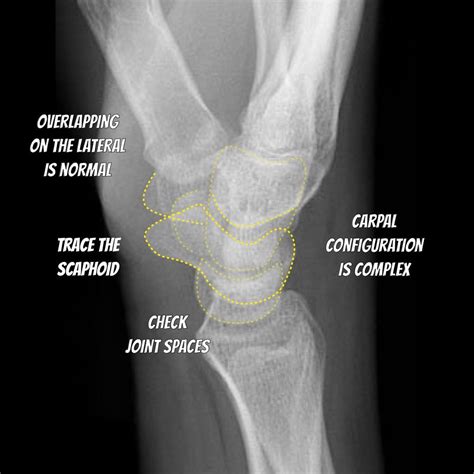

Interpreting a Normal Wrist Xray

Interpreting a Normal Wrist Xray requires a trained eye. Radiologists look for several key features:

• Bone density and structure

• Alignment of the bones

• Presence of fractures or dislocations

• Signs of arthritis or other joint disorders

• Soft tissue abnormalities

• Fractures: Common in the scaphoid, radius, and ulna bones.

• Dislocations: Often involving the lunate or other carpal bones.